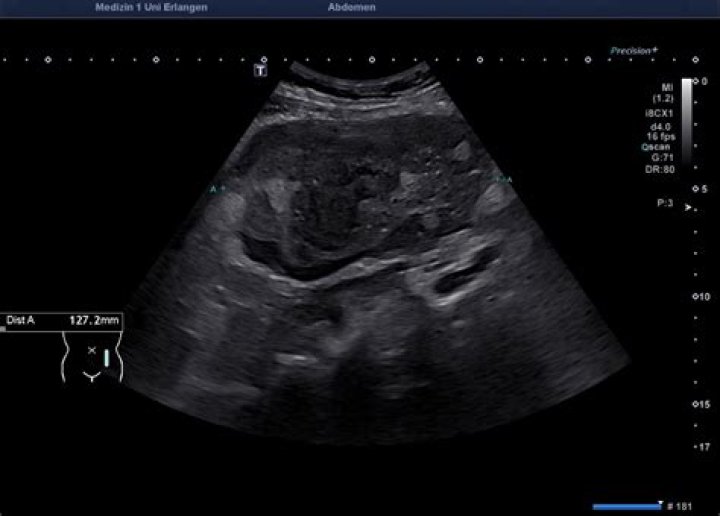

What do lymphoma lymph nodes look like on ultrasound?

On grey scale ultrasound, lymphomatous nodes tend to be round in shape, well-defined, appear hypoechoic and are usually without an echogenic hilus29,,,, features which are similar to most metastatic lymph nodes.

What does an abnormal lymph node look like on ultrasound?

Sonographic features that help to identify abnormal nodes include shape (round), absent hilus, intranodal necrosis, reticulation, calcification, matting, soft-tissue edema, and peripheral vascularity. Metastatic cervical lymph nodes are common in patients with head and neck [1] and non–head and neck [2] cancers.

Lymph nodes in lymphomas may be indistinguishable from reactive lymph nodes in ultrasound, also with the application of color or power Doppler option (Fig. 4) (3, 4).